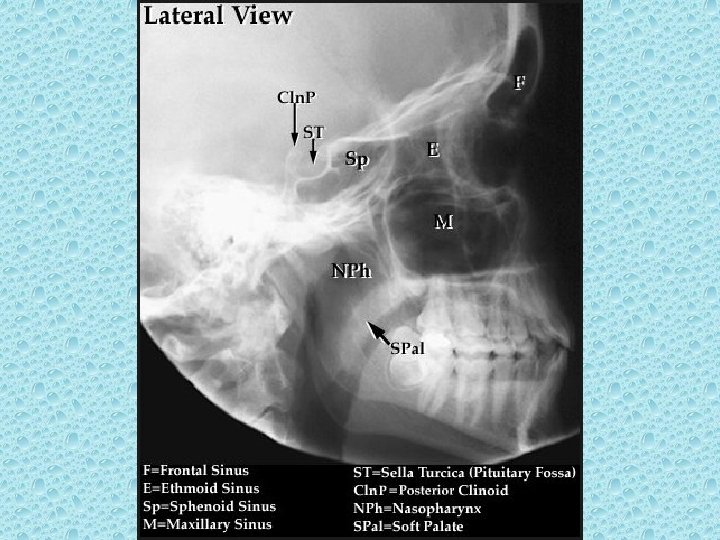

PARANAZAL SİNÜSLER • • Maksiller (2) Frontal Etmoid Sfenoid

SELLA TURSİKA • • • Sfenoid kemik korpusundadır Anterior ve posterior clinoidler Hipofiz fossası Dorsum sella İçerisinde hipofiz bezi bulunur

NAZAL BOŞLUKTAKİ YAPILAR • • Konkalar: alt, orta, üst Meatüsler: Alt, orta, üst Nazal septum Koana